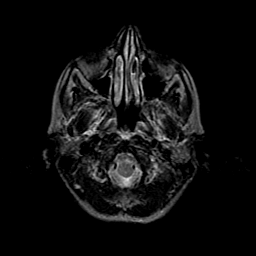

Metastatic bronchogenic carcinoma: T2-weighted MR -- Slice #1

[Home][Help][Clinical] Slice 1